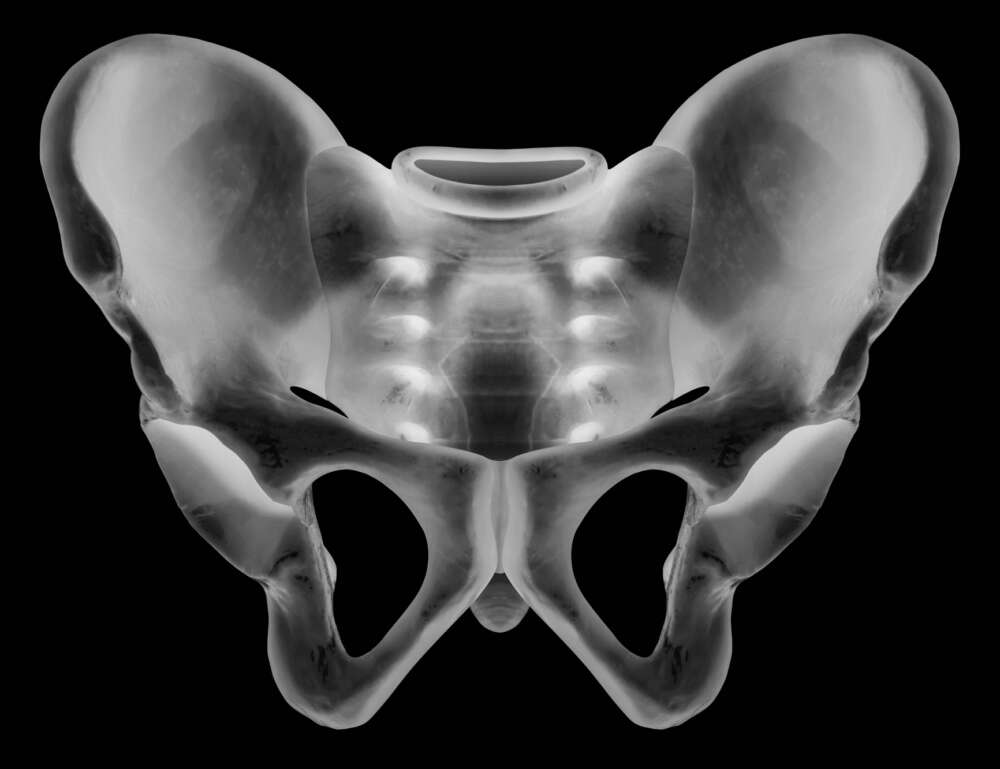

Istockphoto 914140918 1024x1024 Istockphoto 914140918 1024x1024